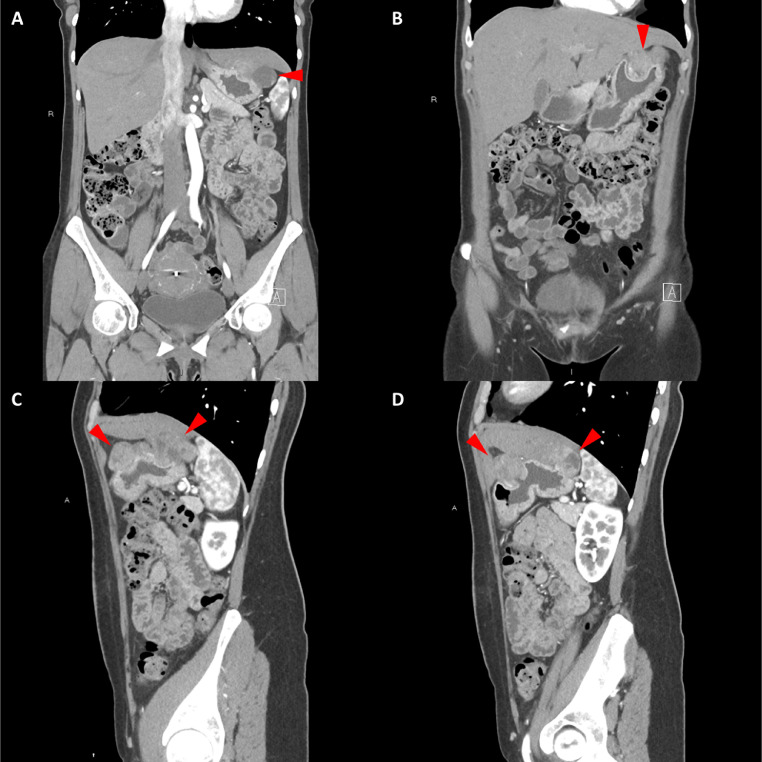

胸部、腹部和骨盆的对比增强动脉和静脉期 CT 显示多个圆形、主要是血管丰富的异质肿块,具有囊性和实性成分,起源于胃底和胃体(图 2-4)。 病变部分呈外生结构,被认为位于粘膜下层。 在颈部多发同步性副神经节瘤的情况下,最初的鉴别诊断包括多发性副神经节瘤、多发性 GIST 以及转移性疾病。

图 3:多个胃肠道间质瘤的冠状和矢状图像。 (A 和 B)冠状动脉相对比增强 CT 图像显示胃贲门产生的外生性肿块。 (C 和 D)矢状动脉相位对比增强图像显示肿块的异质性和外生结构。